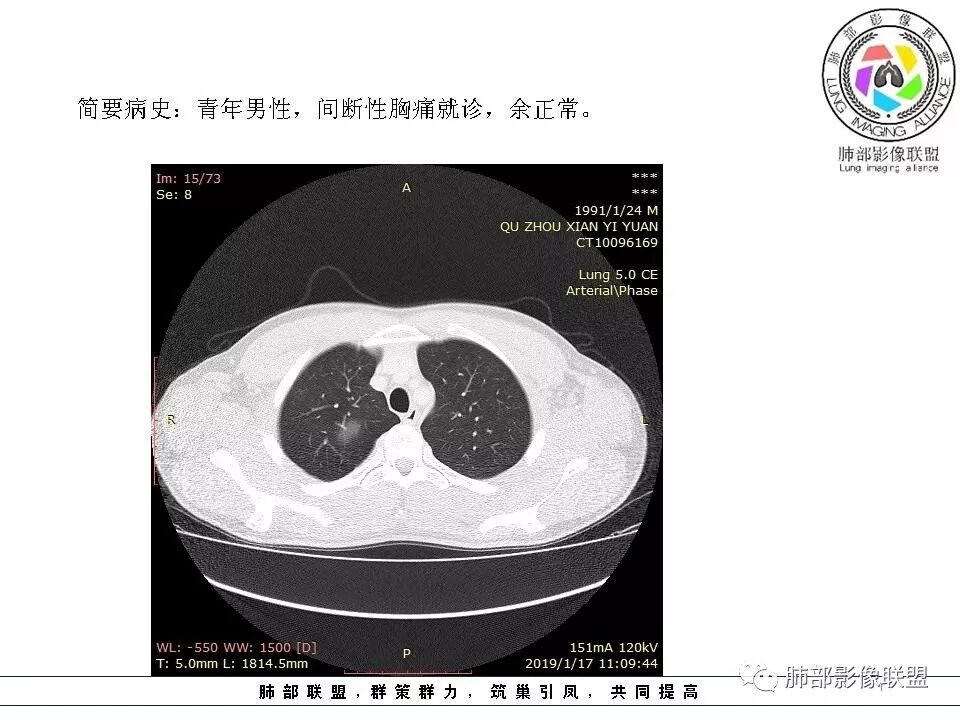

青年男性,间断胸痛;右侧脊柱旁可见一类圆形软组织密度影,密度欠均匀,增强扫描呈轻中度持续强化,邻近肺组织及肺动脉推移,可见肋间动脉供血,部分胸膜下脂肪可见,部分层面似见与右侧椎间孔相连。考虑后纵隔神经源性肿瘤。

青年男性,间断胸痛。右后纵膈脊柱旁软组织占位,形态规则类圆,边缘光整,肺组织受压,D字征,胸膜尾,肋间动脉供血。中度不均匀延迟强化。无支气管进入考虑来源于肺外、肿块与脊柱间未见明显脂肪间隙,考虑来源于胸膜外,考虑神经源性肿瘤,建议穿刺活检。

青年男性,右侧脊柱旁软组织肿块,边缘膨隆,密度不均,临近肺组织受压、胸膜增厚,增强后动脉期呈不均匀强化,并可见肋间动脉供血,延迟期强化较均匀,定位肺外,首先考虑SFT,神经源性肿瘤待排

青年男性,右侧脊柱旁类圆形软组织肿块,边缘光滑,密度欠均,邻近胸膜增厚,肋骨未见异常。定位肺外,良性。考虑神经源性肿瘤

1.右上胸内脊柱旁类圆形肿块,质地似乎比较坚实,密度稍显不均,但未显示明确的坏死。

3.相邻椎间孔未见扩大,也未见块影延入椎管,易起自于神经根的鞘瘤似乎找不到支持点。

可惜未提供矢状位骨窗图像,如在肋骨内下缘观察到压迹有助于肋间神经的鞘瘤的判断,这是因为二者之间密切的毗邻关系。